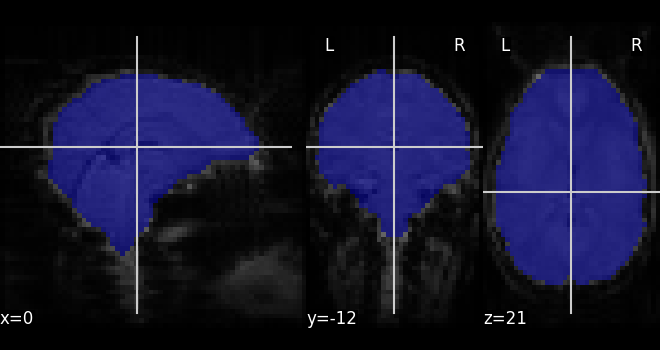

Extracting a brain mask¶

Simple computation of a mask from the fMRI data

from nilearn.masking import compute_epi_mask

mask_img = compute_epi_mask(func_filename)

# Visualize it as an ROI

from nilearn.plotting import plot_roi

plot_roi(mask_img, mean_haxby, colorbar=False)